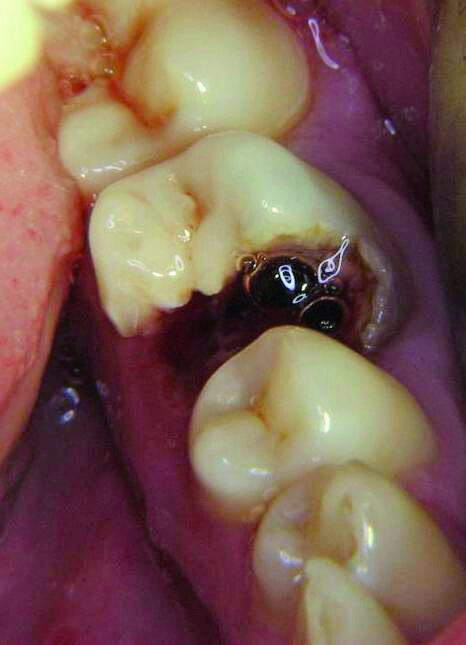

La première molaire supérieure gauche symbolise l’expression de notre sensibilité. Étant donné que cet aspect est souvent réprimé dans notre société moderne, cette dent est aussi très souvent traitée. La première molaire inférieure gauche reflète notre désir d’être aimé. Cette dent est souvent restaurée et est très vite associée à des résultats affligeants. Par exemple, les figures 10a–e montrent une patiente chez qui cette dent s’était fracturée après une rupture sentimentale. Un examen radiographique avait révélé que toutes les autres dents étaient demeurées intactes.